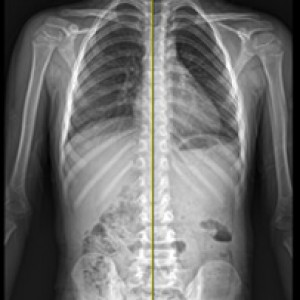

검사부터 다른 당당

“당당은 뼈만 보지 않습니다.”

근육과 근막의 정렬을 함께 진단하며, 풀 스파인 촬영을 통해 머리부터 모든 고관절, 발의 정렬까지 함께 파악하여 개개인에 맞는 전신 치료법을 설계합니다.

디테일하게 자세 패턴을 분석합니다.

7가지 패턴으로

정확한 진단을 합니다.

더 다양한 패턴을 바탕으로 분석 후 계획을 세우기 때문에, 진단과 치료의 정밀도가 다릅니다.

신체 부위별 틀어진 방향, 각도에 따라 카테고리별로 분류한 후, 그에 맞는 치료법을 실시합니다.

전신 엑스레이 검사